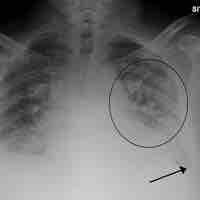

Dead Space: V/Q Mismatch

Dead space is a broken down or blocked region of the lung that produces a mismatch of air and blood in the lungs (V/Q mismatch).